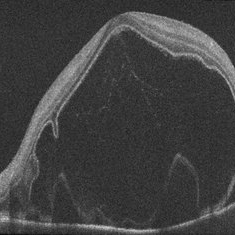

Exudative Detachment of the Macula in Vogt-Koyanagi-Harada Syndrome

Jan 10 2018 by Peter H. Tang, MD, PhD

SD-OCT imaging of an exudative detachment of the macula in a 27-year-old male diagnosed with Vogt-Koyanagi-Harada Syndrome.

Imaging device: Zeiss Cirrus HD-OCT

Condition/keywords: exudative macula detachment, serous retinal detachment, uveitis, Vogt-Koyanagi-Harada